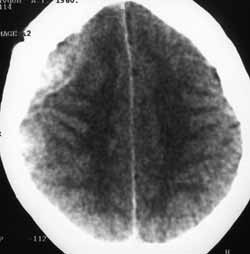

Рис. 10. Плазмоцитома. В правой височно-теменной области конвекситально несколько линзообразных изоденсивных образований, ошибочно принятых за подострые эпидуральные гематомы (в анамнезе ЧМТ).